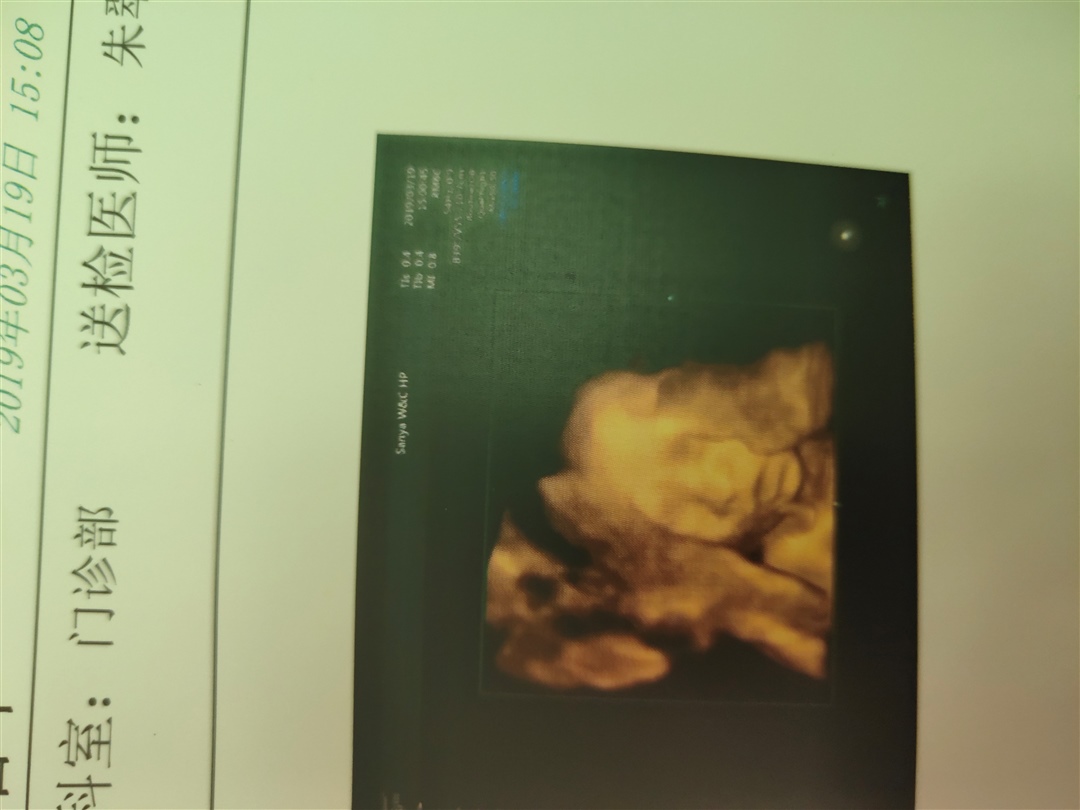

孕19周+6天

接四维一次过